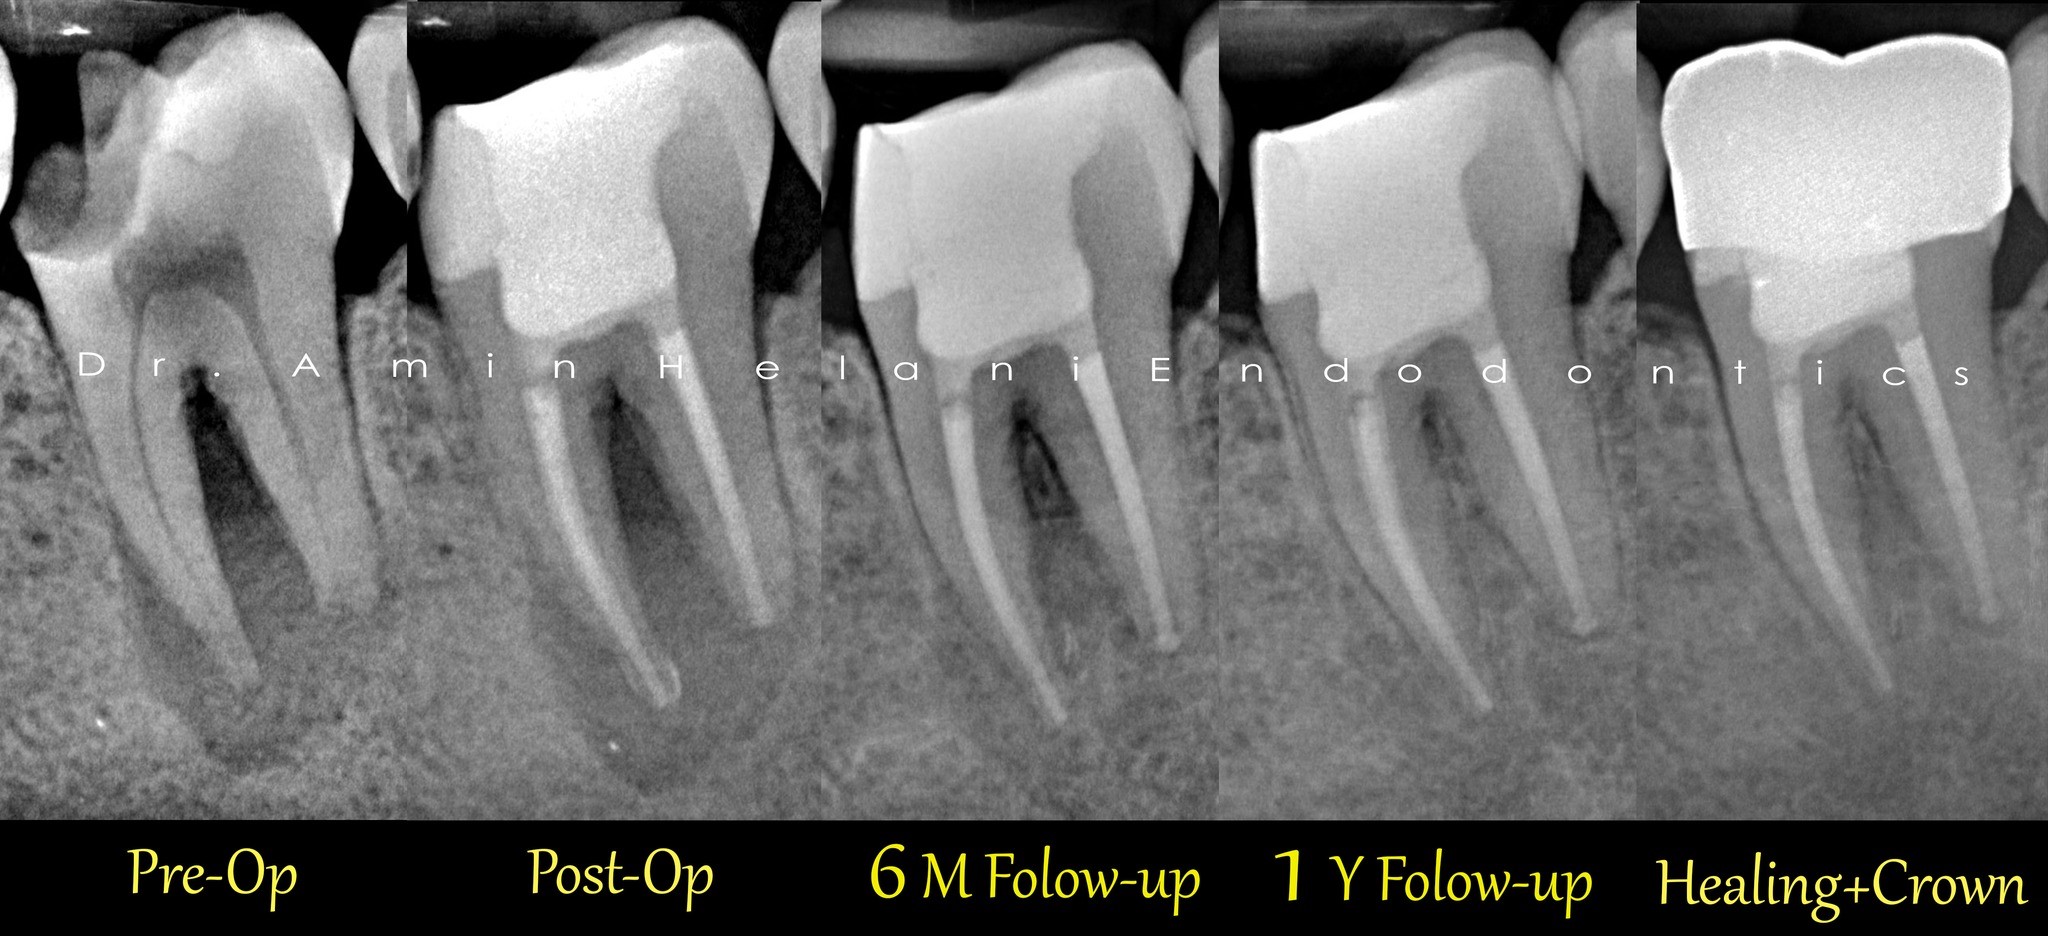

Heilung einer zystischen Läsion